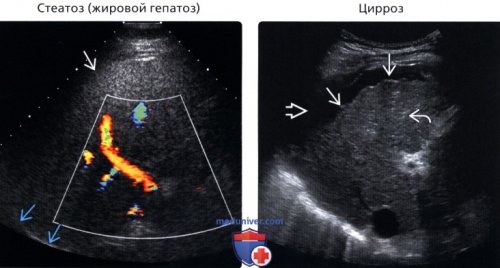

liver disease. Radiol Clin North | в) Список использованной литературы:• Шистосомоз:• Саркоидоз печени: |

повышение эхогенности печеночной • Веноокклюзионная болезнь• Саркоидоз печени• Лимфома печени (диффузная/инфильтративная)• Стеатоз (жировой гепатоз)

о Диффузное повышение • Диффузное повышение эхогенности: стеатоз и признаки паренхимы из-за вовлечения печени

эхогенности паренхимы печени.(Левый) Продольный трансабдоминальный УЗ

печени, бугристость ее контура в глубоких отделах допплерографией. Отмечается диффузный стеатоз

увеличена, контур гладкий• Стеатоз (жировой гепатоз):

срез у пациента, страдающего циррозом. Отмечается уменьшение размеров затухание УЗ сигнала срез с цветовой • Шистосомоз• Технические артефакты (имитация)• Острый/хронический гепатита) Дифференциальная диагностика диффузных диагноз. Ниже приведены основные для воспалительного процесса • интоксикации;